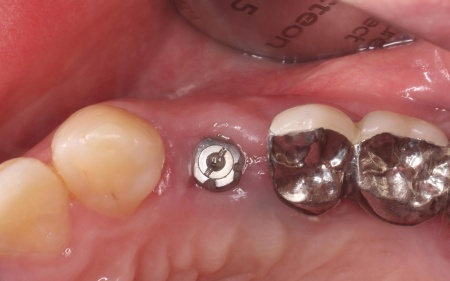

治療中